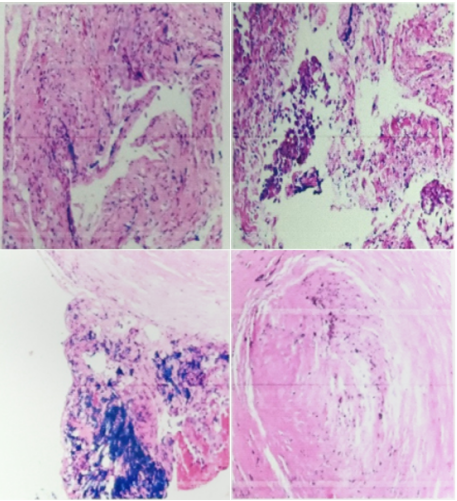

2月8日TBLB病理学(左下肺外基底段左下叶背段)诊断:肺泡上皮无异型,肺泡间隔增宽,纤维组织增生炎细胞浸润,伴碳沫沉着,肺泡腔内见Masson小体及泡沫细胞聚集,呈机化性肺炎改变(图6)

图6  TBLB病理结果(2月8日)

2月9日右侧胸膜结节病理学:镜下见增生间皮样细胞,急、慢性炎细胞浸润,较多嗜酸性粒细胞聚集,胶原化小结节形成(图7)。免疫组化结果支持为间皮增生,灶性呈乳头状增生,较多啫酸性粒细胞聚集、浸润,炎症重(图8)

图7  胸膜结节病理结果(2月9日)